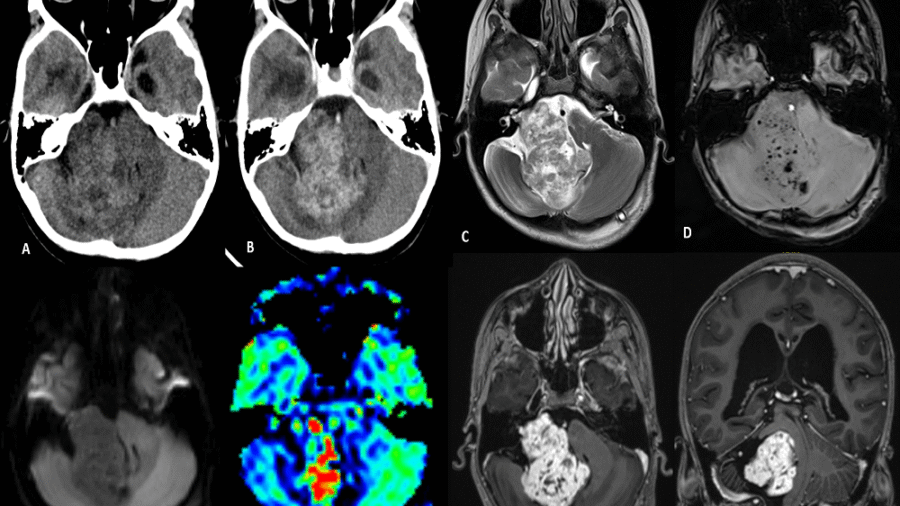

A 30 year old man, presented with complaints of severe headache and vomiting since 4 days.

No history of trauma. No focal neurological deficits.

No significant past history.